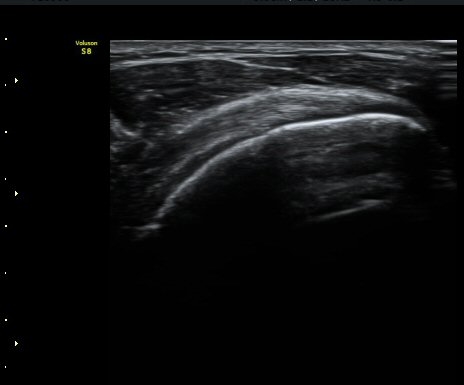

¼ö¾×Àú·ù°¡ °üÂûµÈ´Ù(±×¸² 1, 2). °ß°©ÇÏ±Ù°Ç Á¾´Ü¸é°Ë»ç¿¡¼­ °ß°©ÇϱٰÇÀÇ °üÀý³»ºÎÀ§(±×¸² 3)

¿Í ¼Ò°áÀý »óºÎ(±×¸² 4)¿¡¼­ ƯÀÌ ¼Ò°ßÀ» º¸ÀÌÁö ¾Ê´Â´Ù.